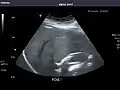

Left kidney